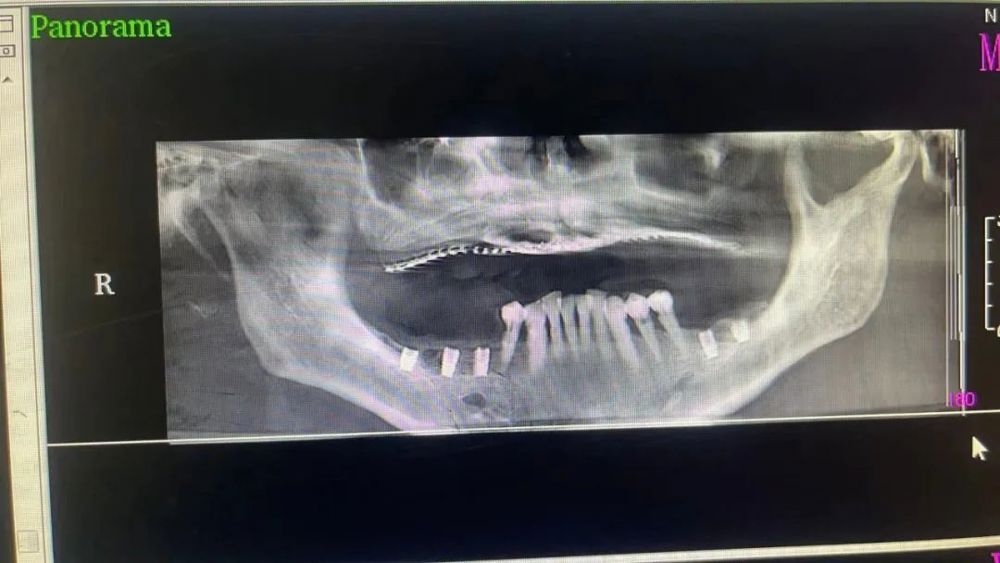

三、種植牙技術

目前,社會上很多人被牙齒缺失所困擾,牙齒缺失不但影響人的咀(jǔ)嚼和語言功能,對於人的麵部美觀也是一種(zhǒng)影響,甚(shèn)至有些人因缺失牙齒而不願意張口說話,種植牙被譽(yù)為人類“第三副牙齒”,因其舒(shū)適、美觀、功能好而被缺牙患者追捧。經衛建委批準,我院(yuàn)於2023年3月18日正式開展種植牙技術,開展當天門診手術7例共計14顆植體,術後1天回訪患者表示無紅(hóng)腫、無疼痛症狀,術後7天回(huí)訪一切良好無異常,術後10天拆線創口愈合良好,自(zì)開展口腔種植手術以(yǐ)來(lái),有(yǒu)許多患者紛紛(fēn)到科裏(lǐ)進行相關谘詢和檢查,更是不斷有患者預約意向種植,我院嚴格按照江西省(shěng)醫療保障局、江西省衛生(shēng)健康(kāng)委員會關(guān)於公布實施口腔種植類醫(yī)療服務價格有關事項的通知—贛醫(yī)保字《2023》3號文件執行操作,在(zài)手術診療中,嚴(yán)格操作流程,減少感染風險。我院口(kǒu)腔種植技術的成功和發(fā)展,不僅完(wán)善了傳(chuán)統(tǒng)牙(yá)齒修複技術的不足,而且在功能與美觀上給了人(rén)們嶄新的體驗,我(wǒ)院(yuàn)致力於提供一站式口(kǒu)腔種植診療(liáo)服務,必將為本縣及周邊缺失牙患者找回(huí)美麗、自信的微(wēi)笑。

手術中

案例一

種植前 種植後